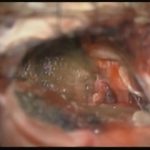

術中写真

摘出 前

摘出 中

摘出 後